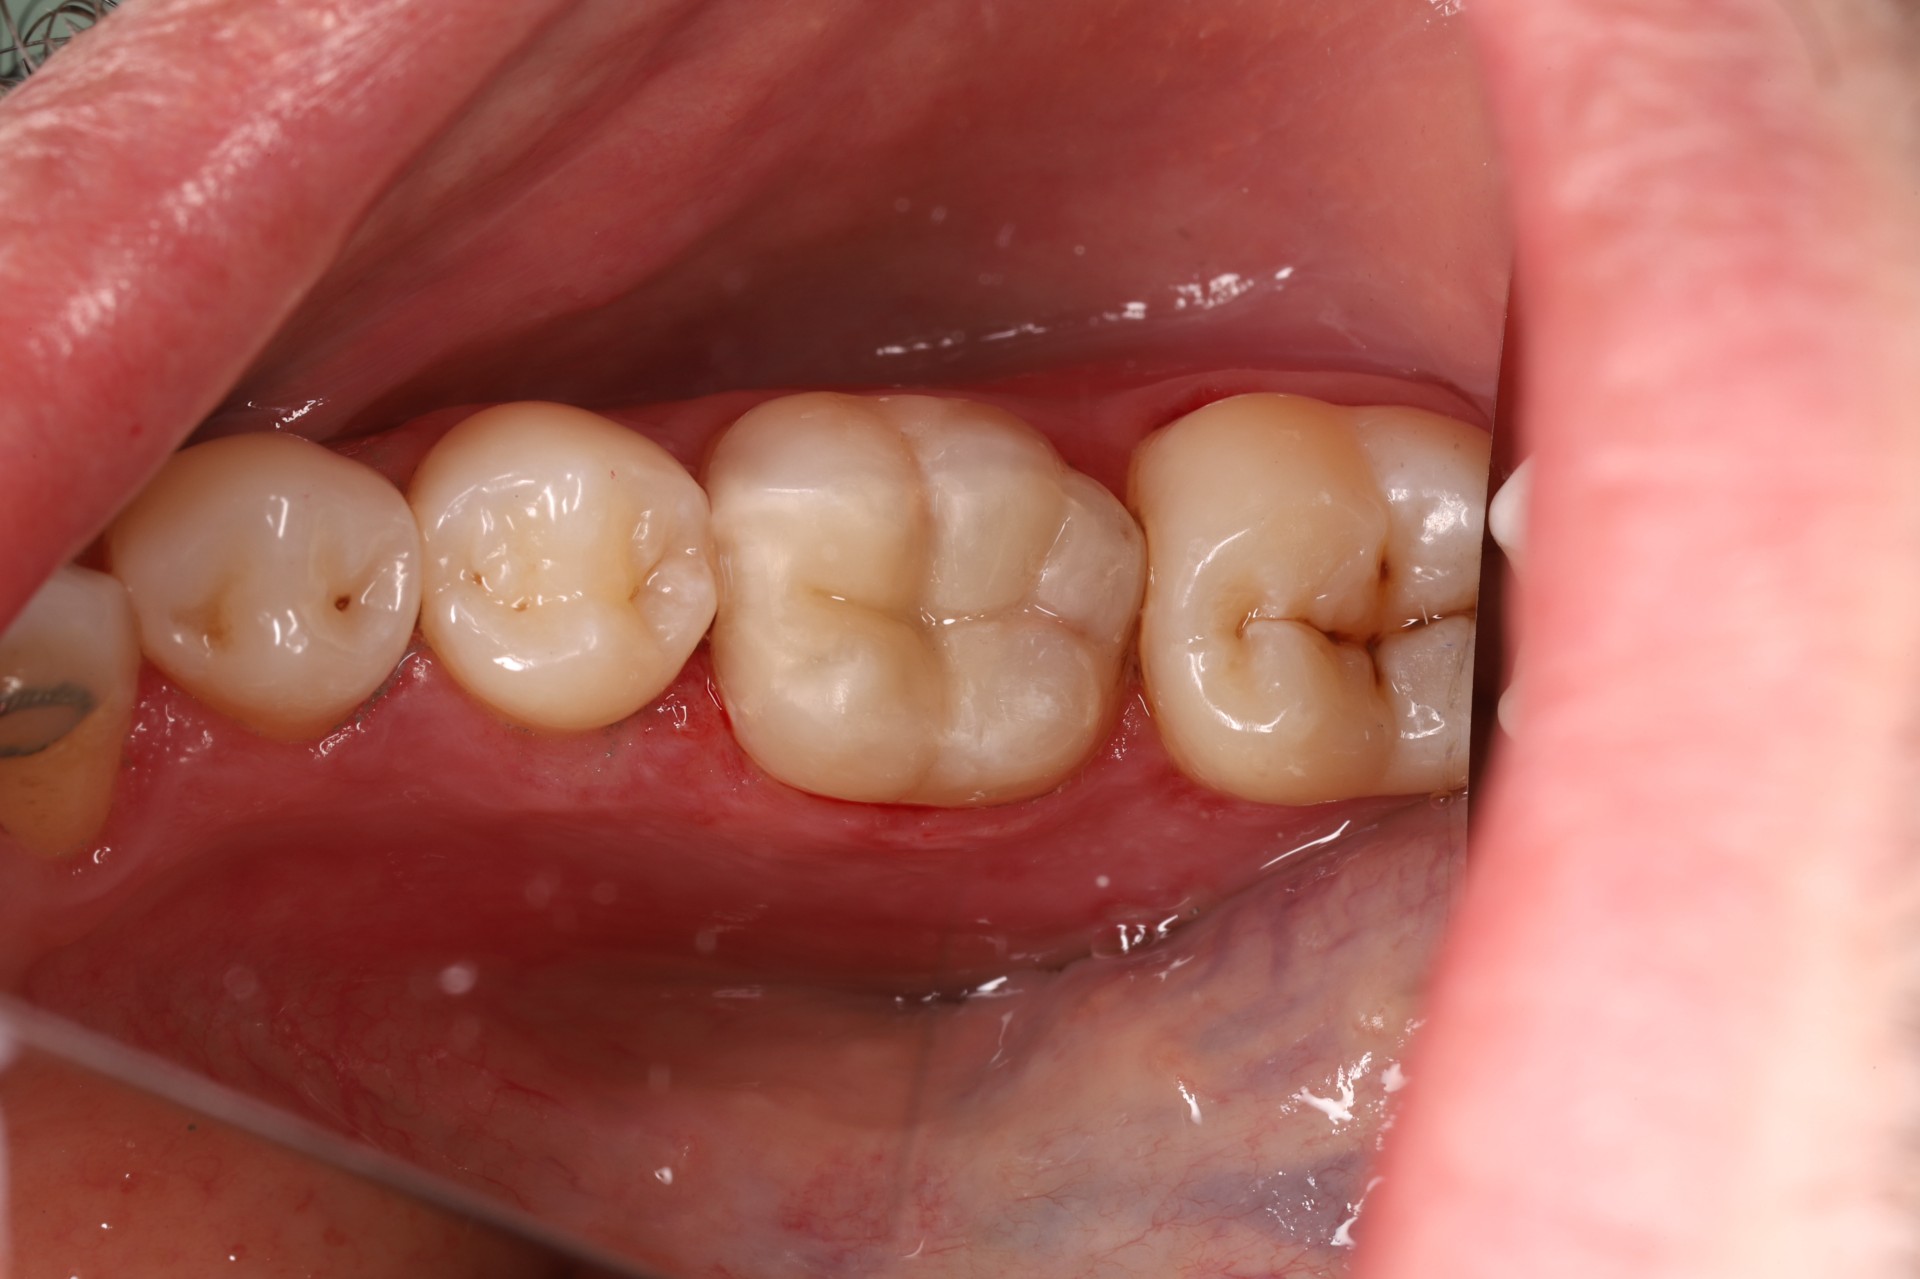

• replacing old metal fillings with a tooth-coloured option

Durable for Everyday Chewing

Modern composites are engineered to withstand normal bite forces and maintain a smooth, glossy surface.

5. Final Polishing and Bite Adjustment

We contour and polish the surface to a high gloss and ensure your bite feels natural in all positions.